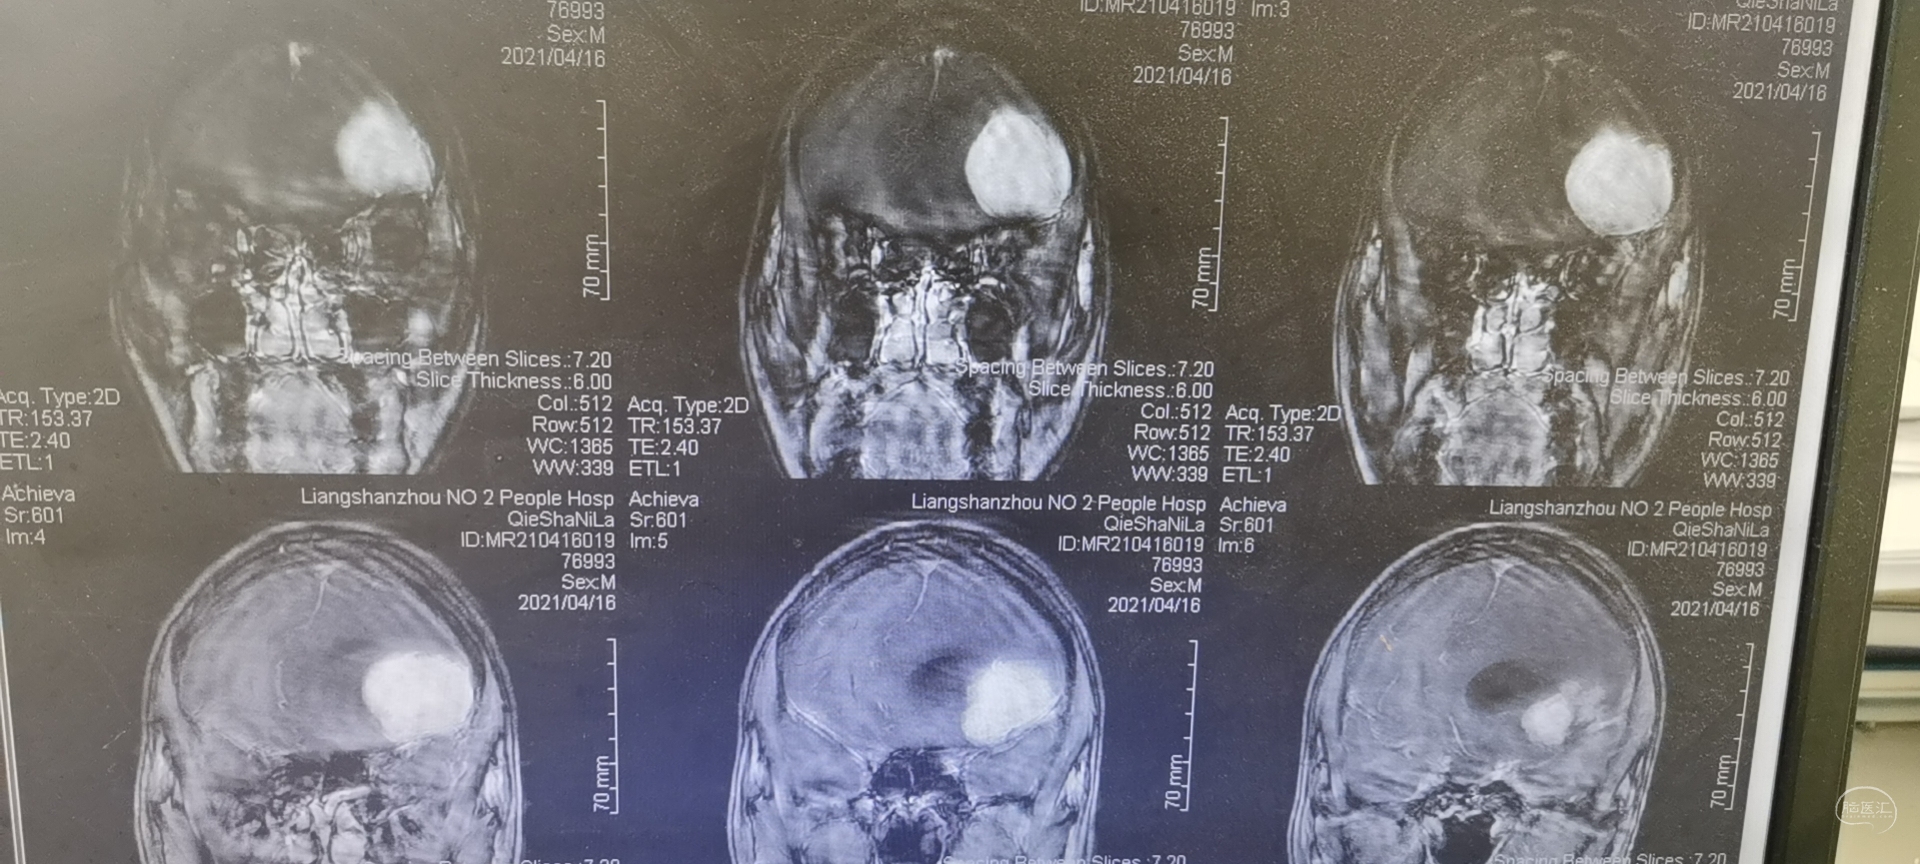

术前头颅MRI检查提示为左侧额叶占位性病变,增强强化均匀,似有脑膜征。考虑为脑膜瘤,蝶骨棘外侧型。

术后头颅MRI检查切除满意